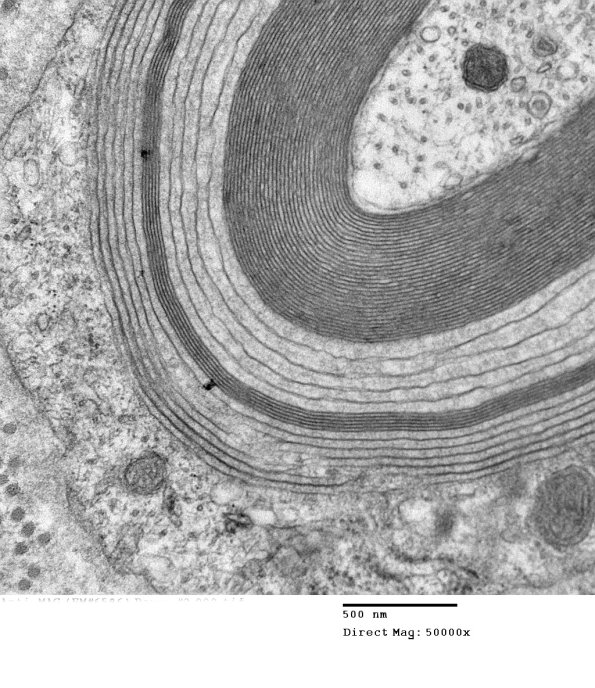

This impressively involved axon shows that the wide-spaced myelin may be separated by intact layers of normal periodicity myelin. (electron micrograph)